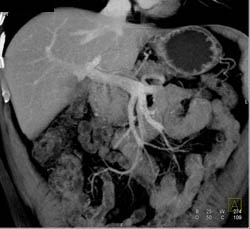

Pancreatic Cancer Encases the SMA